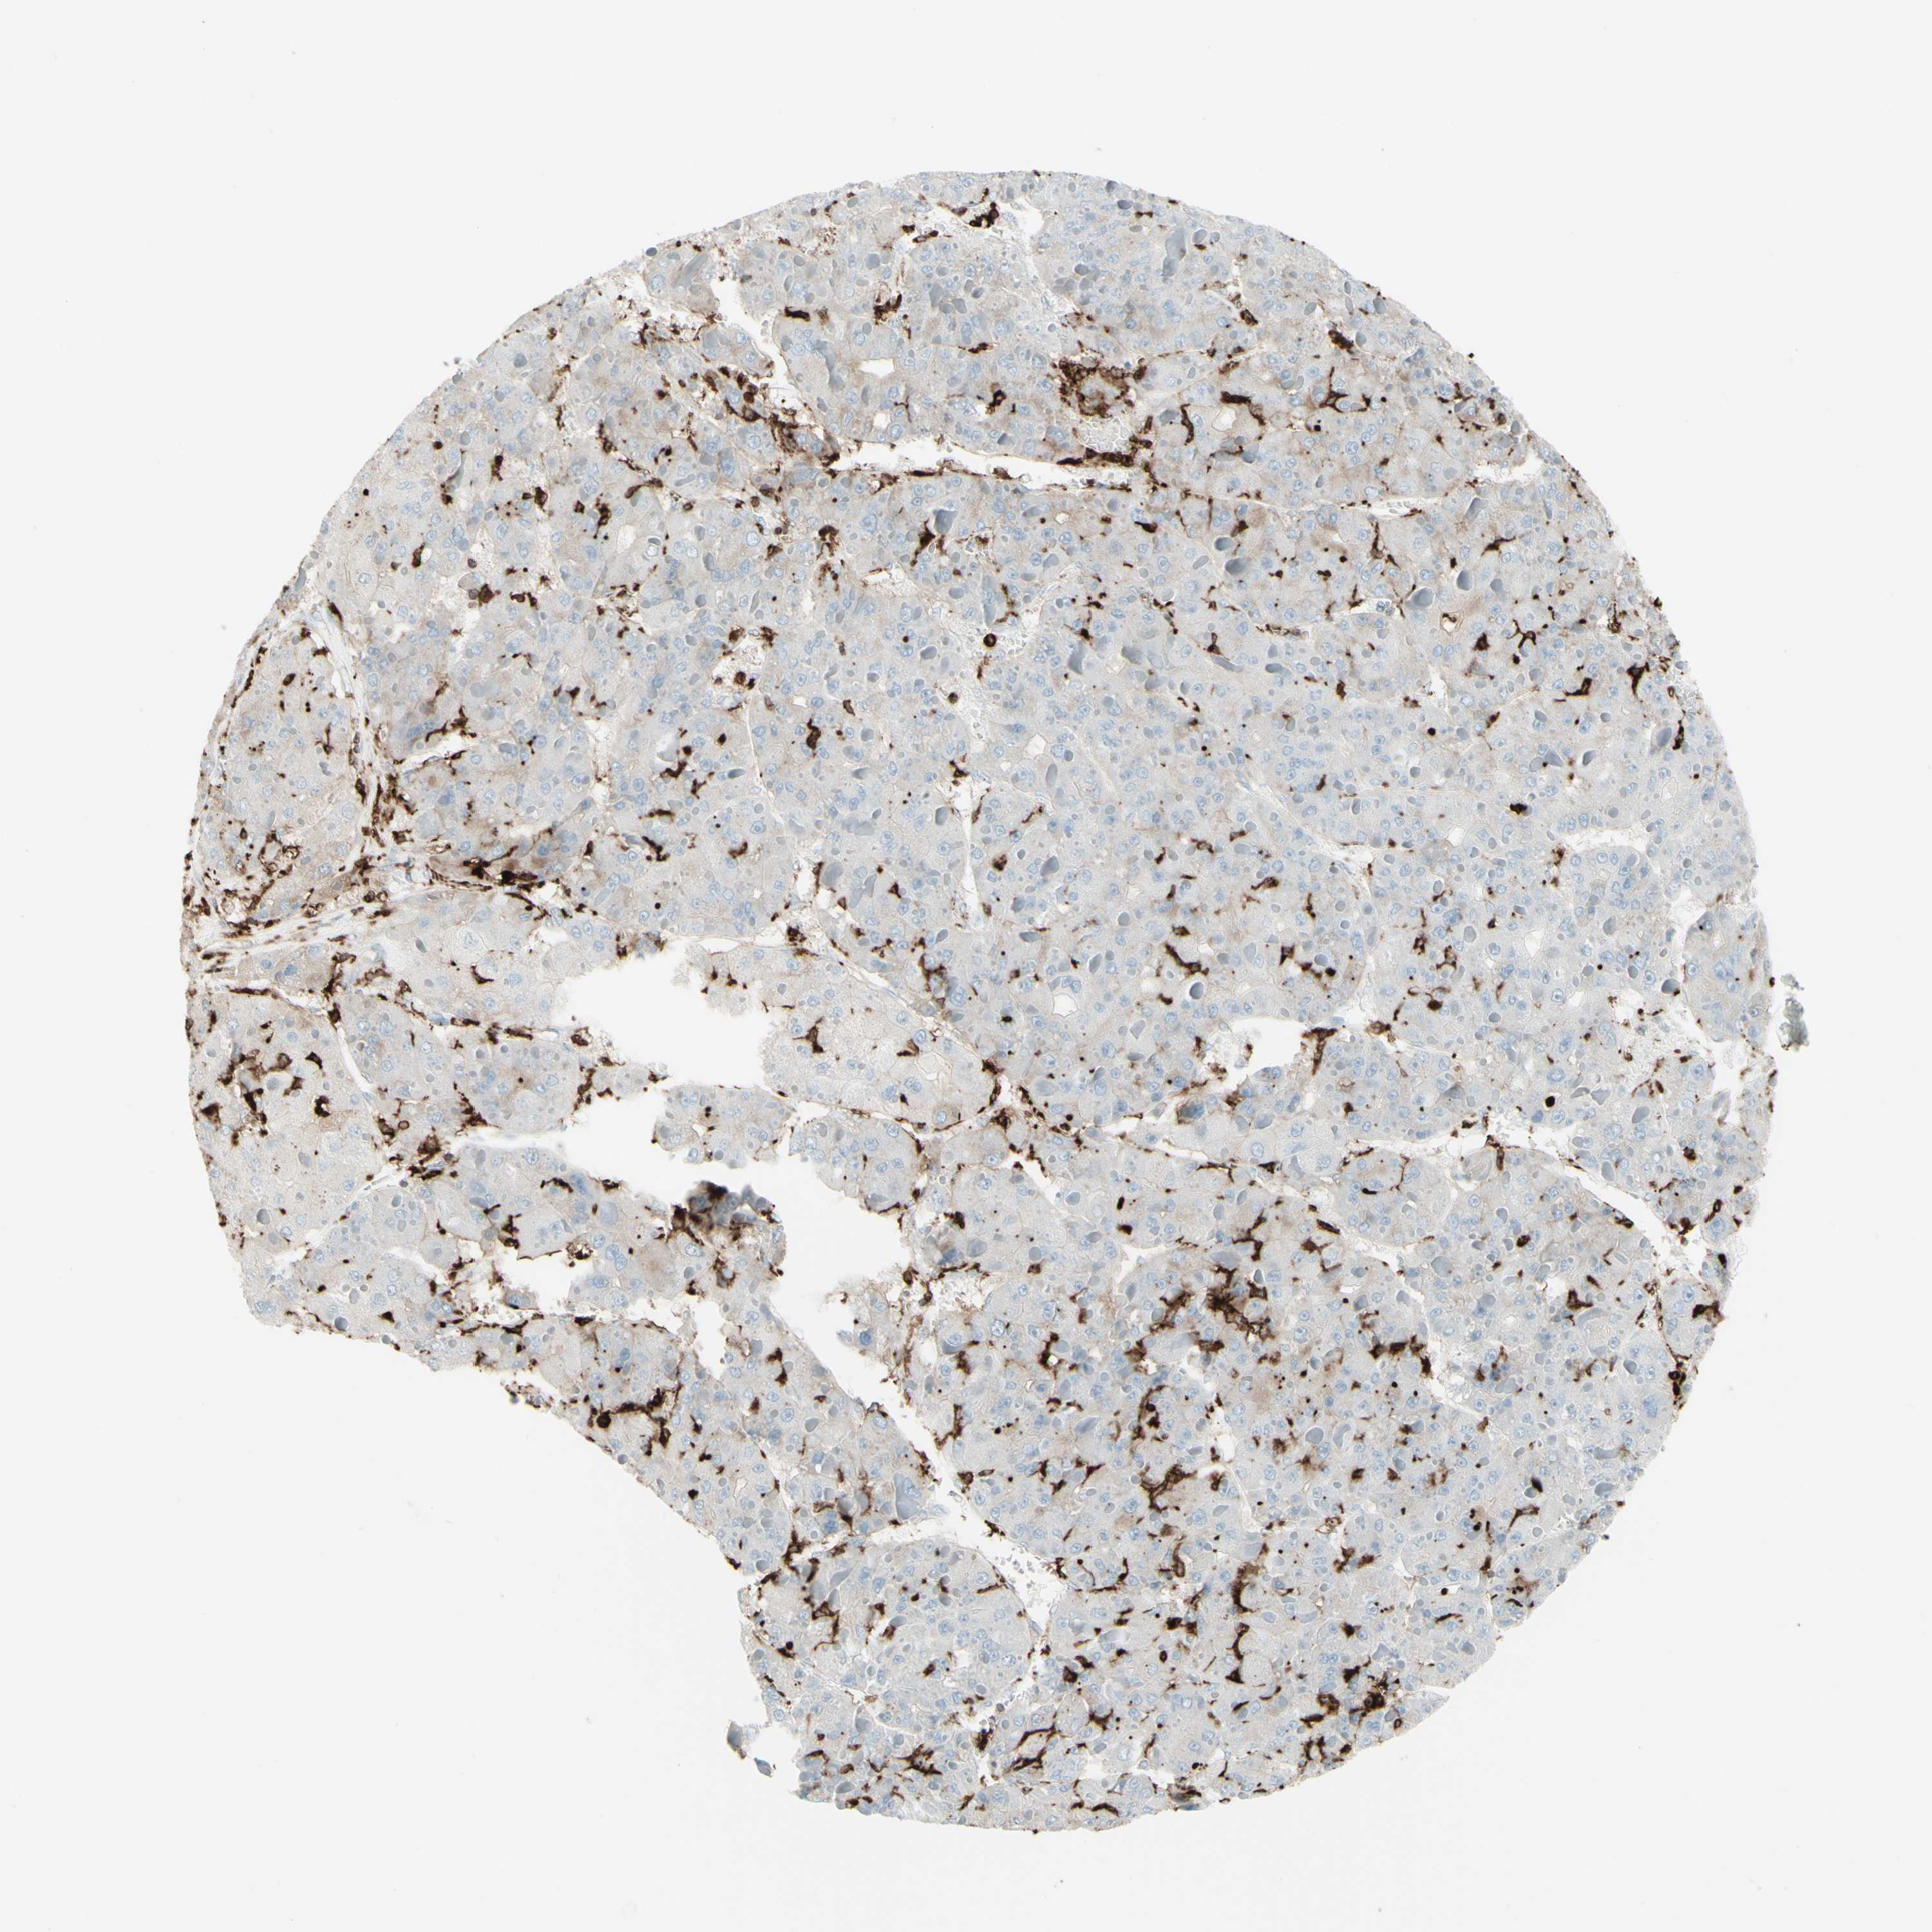

LIVER CANCER - Protein expressioni

A mouse-over function shows sample information and annotation data. Click on an image to view it in a full screen mode. Samples can be filtered based on level of antibody staining by selecting one or several of the following categories: high, medium, low and not detected. The assay and annotation is described here.

Note that samples used for immunohistochemistry by the Human Protein Atlas do not correspond to samples in the TCGA dataset.

Antibody stainingi

Antibody staining in the annotated cell types in the current human tissue is reported as not detected, low, medium, or high, based on conventional immunohistochemistry profiling in selected tissues. This score is based on the combination of the staining intensity and fraction of stained cells.

Each image is clickable and will lead to virtual microscopy that enables deeper exploration of all samples and also displays staining intensity scores, fraction scores and subcellular localization as well as patient and tissue information for each sample.

Antibody HPA011078

Staining

High

Medium

Low

Not detected

Intensity

Strong

Moderate

Weak

Negative

Quantity

>75%

75%-25%

<25%

None

Location

Nuclear

Cytoplasmic/membranous

Cytoplasmic/membranous,nuclear

Cholangiocarcinoma

Carcinoma, Hepatocellular, NOS